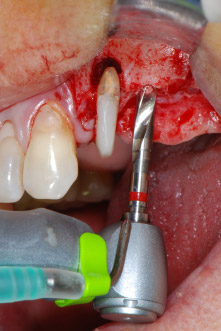

However, we maintained our initial plan to retain both teeth as temporary bridge abutments during the six-months osseointegration period of the implants. At reentry, the situation would have to be reassessed. First, in an attempt to manage the endo-perio problem, the remaining root surface was carefully debrided with piezoelectric equipment (Piezomed, W&H, used with the spatula-shaped insert S1, originally designed for erosion of the lateral sinus wall) (Fig. 4).

Then the apex was abraded with the same instrument to remove residual infected apical tissue and to reduce possible accessory root-canal ramifications (apicoectomy) (Fig. 5). A retrograde filling was not necessary because the orthograde filling had just been revised.

periodontium

Fig. 4: To preserve the tooth as a temporary abutment, the periodontium was debrided with piezoelectric equipment …

buccal apex of tooth 24

Fig 5: ... and the buccal apex of tooth 24 was abraded with the same instrument (apicoectomy).

implant motor

Fig. 8: Rotary preparation of the implant bed short of the floor of the maxillary sinus at position 25, carried out with an updated implant motor.

Implant beds were prepared at sites 25 and 26 with rotary instruments, used in a contra-angle handpiece with a 20 : 1 transmission ratio with an updated powerful implant motor (Implantmed, W&H) (Fig. 8).

The final preparation next to the sinus was again carried out with a piezoelectric instrument (Piezomed, insert S2).